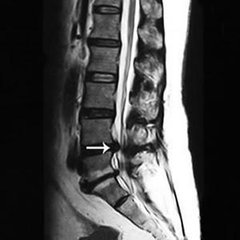

退变性腰椎管狭窄。退变性腰椎管狭窄症是一种因腰椎中央椎管、神经根管、侧隐窝或椎间孔退行性改变,致使骨性结构和(或)纤维结构形态与容积发生异常,单一或多平面中一处或多处管腔内径出现狭窄而引起神经和血管等组织活动空间减小,并出现腰骶部或下肢疼痛的临床综合征,可伴有或不伴有腰腿痛。一般多发生于60~70岁老年人,发病率为1.7%~10.0%,女性多于男性。 >>>患上颈椎管狭窄症怎么办?能不能治疗?

退变性腰椎管狭窄症退变可以开始于任何一个关节,通常始于椎盘。椎间盘因为退变而塌陷,椎间隙变狭窄后,上关节突上移前倾,因摩擦进而增生肥大,椎间孔可以出现狭窄。退变性腰椎管狭窄症一般主要有以下症状:

第四,如合并椎间盘突出者,则有椎间盘突出症状及体征。 第五,X线检查可显示腰椎管矢径和横径变小,及椎体退行性变。》》》如何确诊自身病情,点击咨询